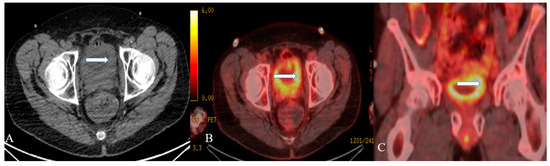

Figure 10. A 48-year-old female with urinary bladder NENs. Axial CT without contrast (A), axial (B), and coronal (C) reconstruction fused PET/CT images show thickened urinary bladder wall (arrows), which is most evident on the left side. The maximum thickness measures 2.4 cm and has an SUV of 8.2. Pathology revealed small-cell neuroendocrine carcinoma of the urinary bladder.